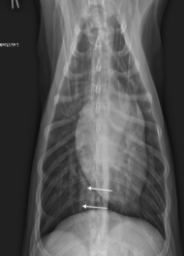

What sign is this?

Bacpack sign - L. atrial enlargement